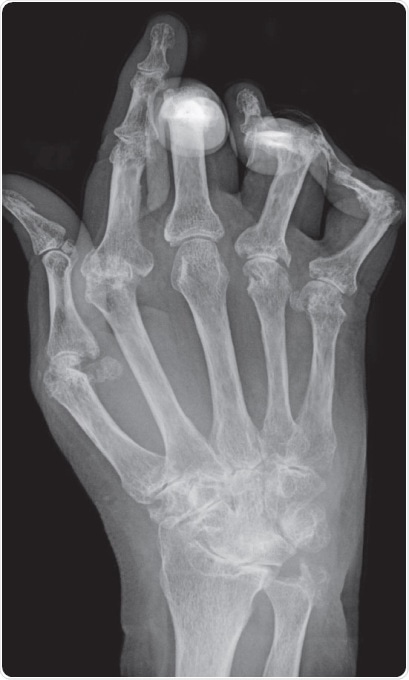

Typical X-ray of hand with advanced rheumatoid arthritis. Bone erosion, cartilage degradation and bone displacement are classic features of this disease (from Bernd Brägelmann via Wikimedia Commons)

Figure 1. Typical X-ray of a hand with advanced rheumatoid arthritis. Bone erosion, cartilage degradation, and bone displacement are classic features of this disease (from Bernd Brägelmann via Wikimedia Commons)